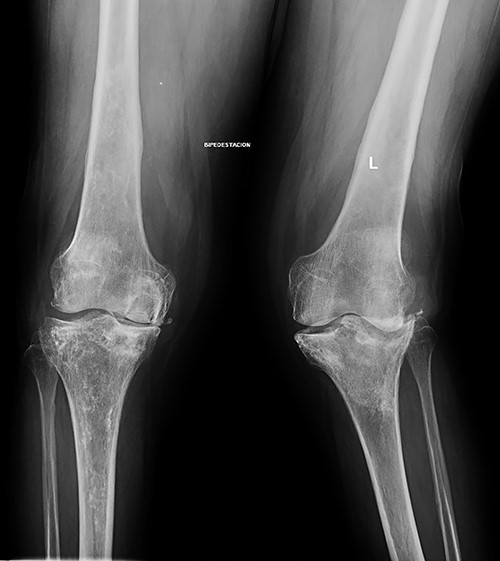

She was referred to our Service to evaluate progressive and disabling pain in both knees. Physical examination revealed bilateral quadriceps atrophy with valgus laxity in the left knee and varus laxity in her right knee. Range of motion (ROM) in both knees was 0°–100°. Standing radiographs showed a pattern of diffuse osteopenia and necrosis (Fig. 1).

Initial both-legs standing radiographs of the knee. It showed a pattern of diffuse osteopenia with areas of sclerosis, lateral extended bone reaction and decreased lateral articular space (Kellgren–Lawrence 3) in the left knee. Bone necrosis with decreased medial articular space (Kellgren–Lawrence 3) were observed in the right knee.